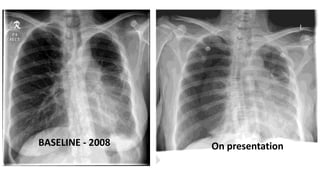

CASE 1

• 34yrs/Malay/Male

• No known medical illness

• Ex-smoker 20 pack years (

stopped 4/12, now on e-cigarettes)

• C/O Shortness of breath

and left sided pleuritic chest

pain x 3 days

O/E

• Mildly tachypnoeic RR

24/min

• Pulse: 78/min BP 147/85

mmHg SpO2 100% NP

• Lungs: Reduced air entry on

left side, hyperresonant on

percussion.

CASE 1.. 34yrs/Male/ex-smoker

CXR – on presentation CXR – post left chest tube